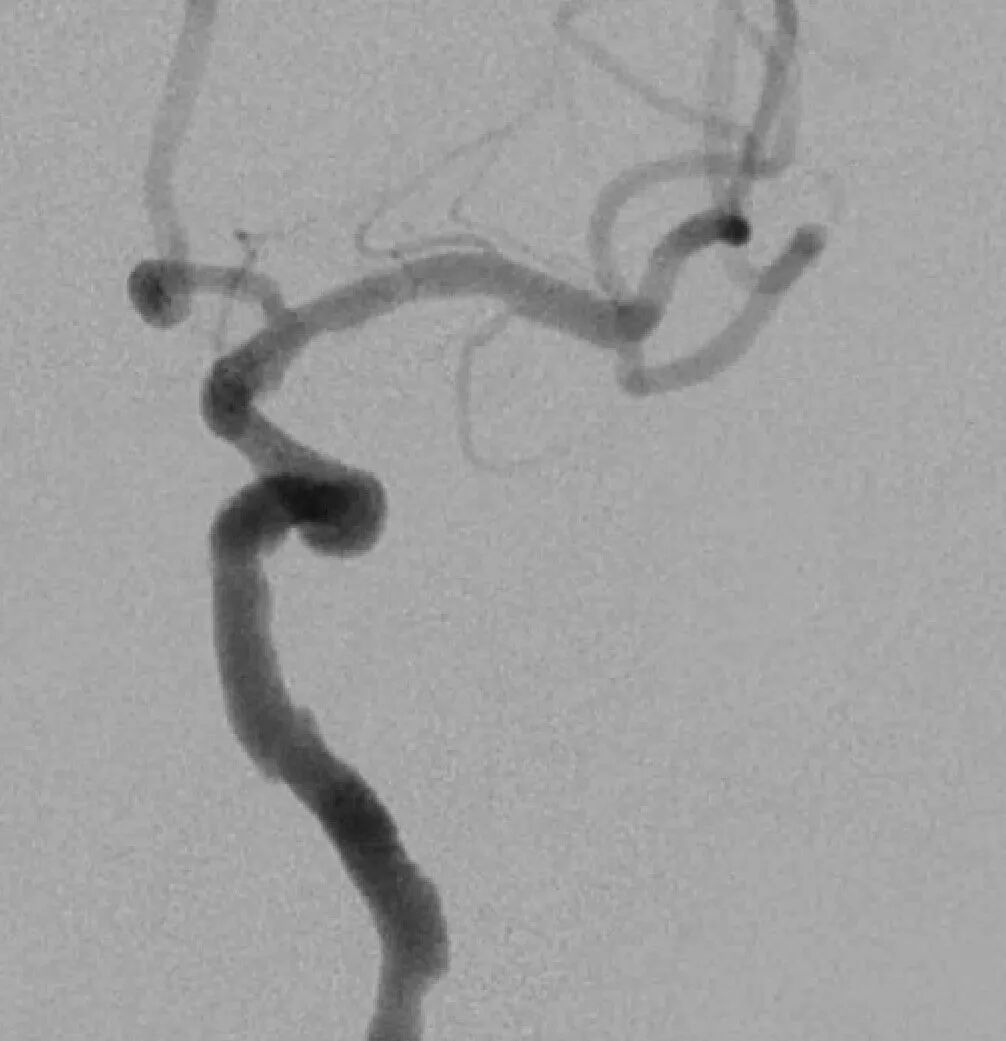

脑血管造影提示右侧颈内动脉颅内段多发动脉瘤(反主动脉弓)

脑血管造影提示右侧颈内动脉颅内段多发动脉瘤

4mm×30mm Streamline

术后4月余随访:多发动脉瘤均未见显影,远端残余轻度狭窄

术前术后对比